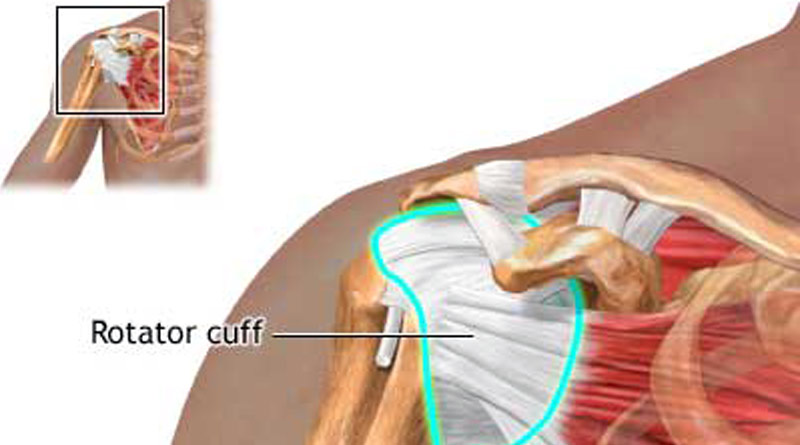

Фотографии мышц ротаторной манжеты плеча